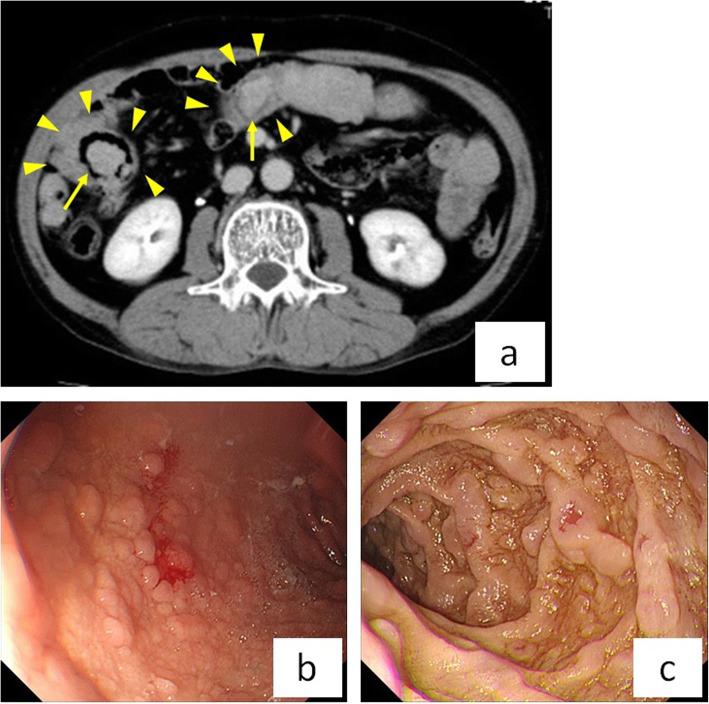

A 62-year-old male was hospitalized for treatment of deep vein thrombosis and pulmonary embolism. In the small intestine, computed tomography showed three small polyps with intussusceptions. Since the patient had gastrointestinal polyposis and pigmentation of his lips, fingers, and toes, he was diagnosed with PJS. After an inferior vena cava filter was placed, he underwent laparoscopic-assisted surgery. The polyps causing intussusception were resected as far as possible without intestinal resection, since they had caused progressive anemia and might cause intestinal obstruction in the future. The patient was discharged from the hospital on postoperative day 9 without complications.

一名 62 岁男性因深静脉血栓形成和肺栓塞住院治疗。小肠计算机断层扫描显示有三个带肠套叠的小息肉。由于患者有胃肠道息肉和嘴唇、手指和脚趾的色素沉着,因此被诊断为 PJS。在下腔静脉滤器放置后,他接受了腹腔镜辅助手术。尽可能地切除引起肠套叠的息肉,而不进行肠切除术,因为它们已导致进行性贫血,并可能在将来引起肠梗阻。患者术后第 9 天出院,无并发症。